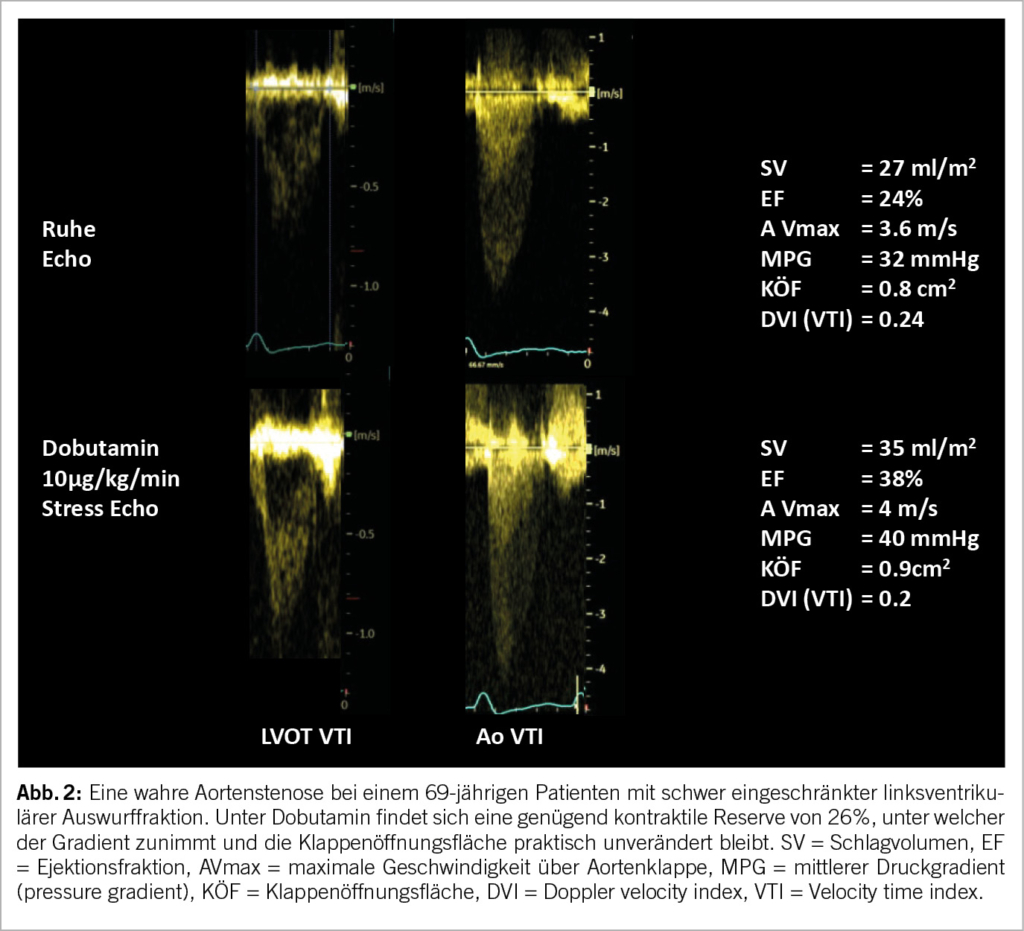

Die häufigste Indikation betrifft dabei eine schwere low-flow, low-gradient Aortenklappenstenose. Wenn eine solche diagnostiziert wird (systolischer mittlerer Druckgradient <40mmHg, Klappenöffnungsfläche ≤ 1cm2, linksventrikuläre Ejektionsfraktion (LVEF) < 50%, indexiertes Schlagvolumen ≤ 35ml/m2), sollte eine Dobutamin-SE durchgeführt werden. In Anwesenheit einer kontraktilen Reserve (= mindestens 20% Zunahme des Schlagvolumens) kann eine echte (Abb. 2) von einer pseudo-schweren Aortenstenose unterschieden werden, was eine klare IB Indikation für eine Intervention darstellt (8). Der Belastungstest kann Symptome bei vermeintlich asymptomatischer Aortenstenose aufdecken. Die physikalische SE liefert dabei prognostische Informationen. Bei einer über 20 mmHg erhöhten Zunahme des systolischen Druckgradienten wird eine frühe Intervention beim niedrigen peri-prozeduralen Risiko im Herzteam empfohlen (8, 9).